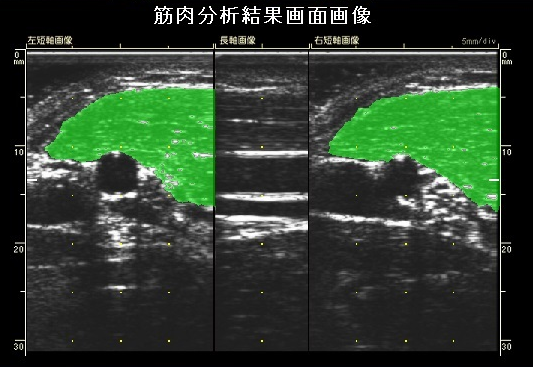

新機能:筋肉分析

ユネクスイーエフはFMDの値と共に、上腕二頭筋の筋肉量と筋質(霜降り度)が算出可能です。